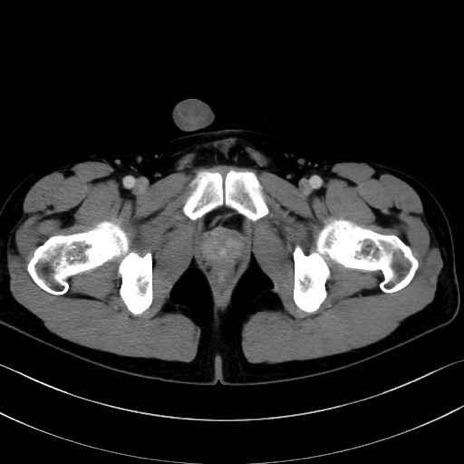

5. 大腿前面(大腿四頭筋群・伸筋群)

縫工筋 (Sartorius)

大腿直筋 (Rectus femoris)

外側広筋 (Vastus lateralis)

中間広筋 (Vastus intermedius)

6. 大腿内側(内転筋群)

恥骨筋 (Pectineus)

長内転筋 (Adductor longus)

短内転筋 (Adductor brevis)